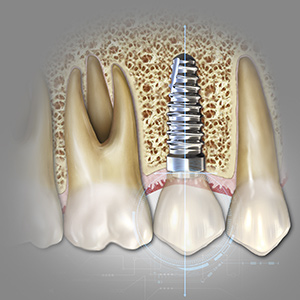

Implantology Pathways

This Compendium eBook features features a continuing education (CE) article on the use of subcrestal implantoplasty for the treatment of peri-implantitis. This eBook also includes a case report article on a novel, minimally invasive technique to reconstruct class III sockets with simultaneo...

Implantology Advances

This Compendium eBook offers a continuing education (CE) article on partial extraction therapy in implant dentistry, with an emphasis on the biologic and anatomic conditions necessary for optimal outcomes with implant surgery. This eBook also includes a case report describing a strategy for...

Implantology Solutions

Friday, March 4, 2022

This Compendium eBook offers a continuing education (CE) article that examines treatment planning for full-arch reconstruction with implant overdentures. A long-term case report is also featured in this eBook, highlighting the steps involved in a full-arch reconstruction using transitional ...

Breakthroughs in Dental Implantology

Wednesday, November 24, 2021

This Compendium eBook offers a continuing education (CE) article on the treatment of retrograde peri-implantitis (RPI), a rare complication of implant placement that may interfere with implant survival. In addition, this eBook includes a case report on a novel approach for improving free gi...

Developments in Implantology

Tuesday, March 9, 2021

This Compendium eBook features a continuing education (CE) article that considers the rationale for graftless alternatives, as well as the data supporting the use of various graftless protocols. In an accompanying clinical materials article, the author addresses modifications in the dental ...

Innovations in Implantology

Monday, November 23, 2020

This Compendium eBook offers a continuing education (CE) article that explores implant abutment and restoration design with respect to risk factors for peri-implant disease. A second article covers minimally invasive extraction site management with dehydrated deepithelialized human amnion/c...

Spotlight on Implantology

Thursday, November 7, 2019

This special Compendium eBook on implant-related topics puts the spotlight on osseodensification, providing the opportunity for readers to receive continuing education (CE) credit by taking a quiz on one or both articles in a two-part series.

Today's Trends in Implantology

Wednesday, March 20, 2019

This special eBook from Compendium presents two continuing education (CE) articles on procedures in implantology. The first CE provides a systematic treatment planning protocol for an implant-supported fixed prosthesis for patients with an edentulous maxilla. The second CE offers 10 keys fo...

Advances in Implantology

Wednesday, October 10, 2018

As the number of older Americans grows, edentulism is likely to be an increasing problem here. To aid dental professionals in keeping up-to-date on implantology, this special Compendium eBook offers two continuing education (CE) articles and a case report on a concept for addressing the nee...

Current Topics in Implantology

Thursday, March 29, 2018

This special Compendium eBook is aimed at helping clinicians expand their implant dentistry knowledge and improve their skills.The first CE article discusses risk indicators and prevention of implant soft-tissue complications. The second CE article explains the risks and benefits of periodontal prob...

Updates in Implantology

Wednesday, December 13, 2017

The special Compendium eBook explores factors for implant success. According to the authors of our first CE article, there are many factors that affect primary implant stability. The authors focus on the impact of insertion torque on achieving predictable osseointegration. Our second CE article desc...

Decision Making in Implantology

Wednesday, January 25, 2017

Earn 4 FREE CEU! Practitioners have many factors to consider to ensure successful results. This eBook features two CE articles by some of Compendium’s top contributing authors and highlights two critical topics that will impact virtually any dental implant practitioner.

Implantology

Monday, November 7, 2016

Earn 4 FREE CEU! This eBook features three articles focusing on implant solutions. The role of narrow-diameter implants as an option for provisional and definitive fixed restorations is discussed in two offerings, while the third article reviews risk factors and treatments for peri-implantitis.